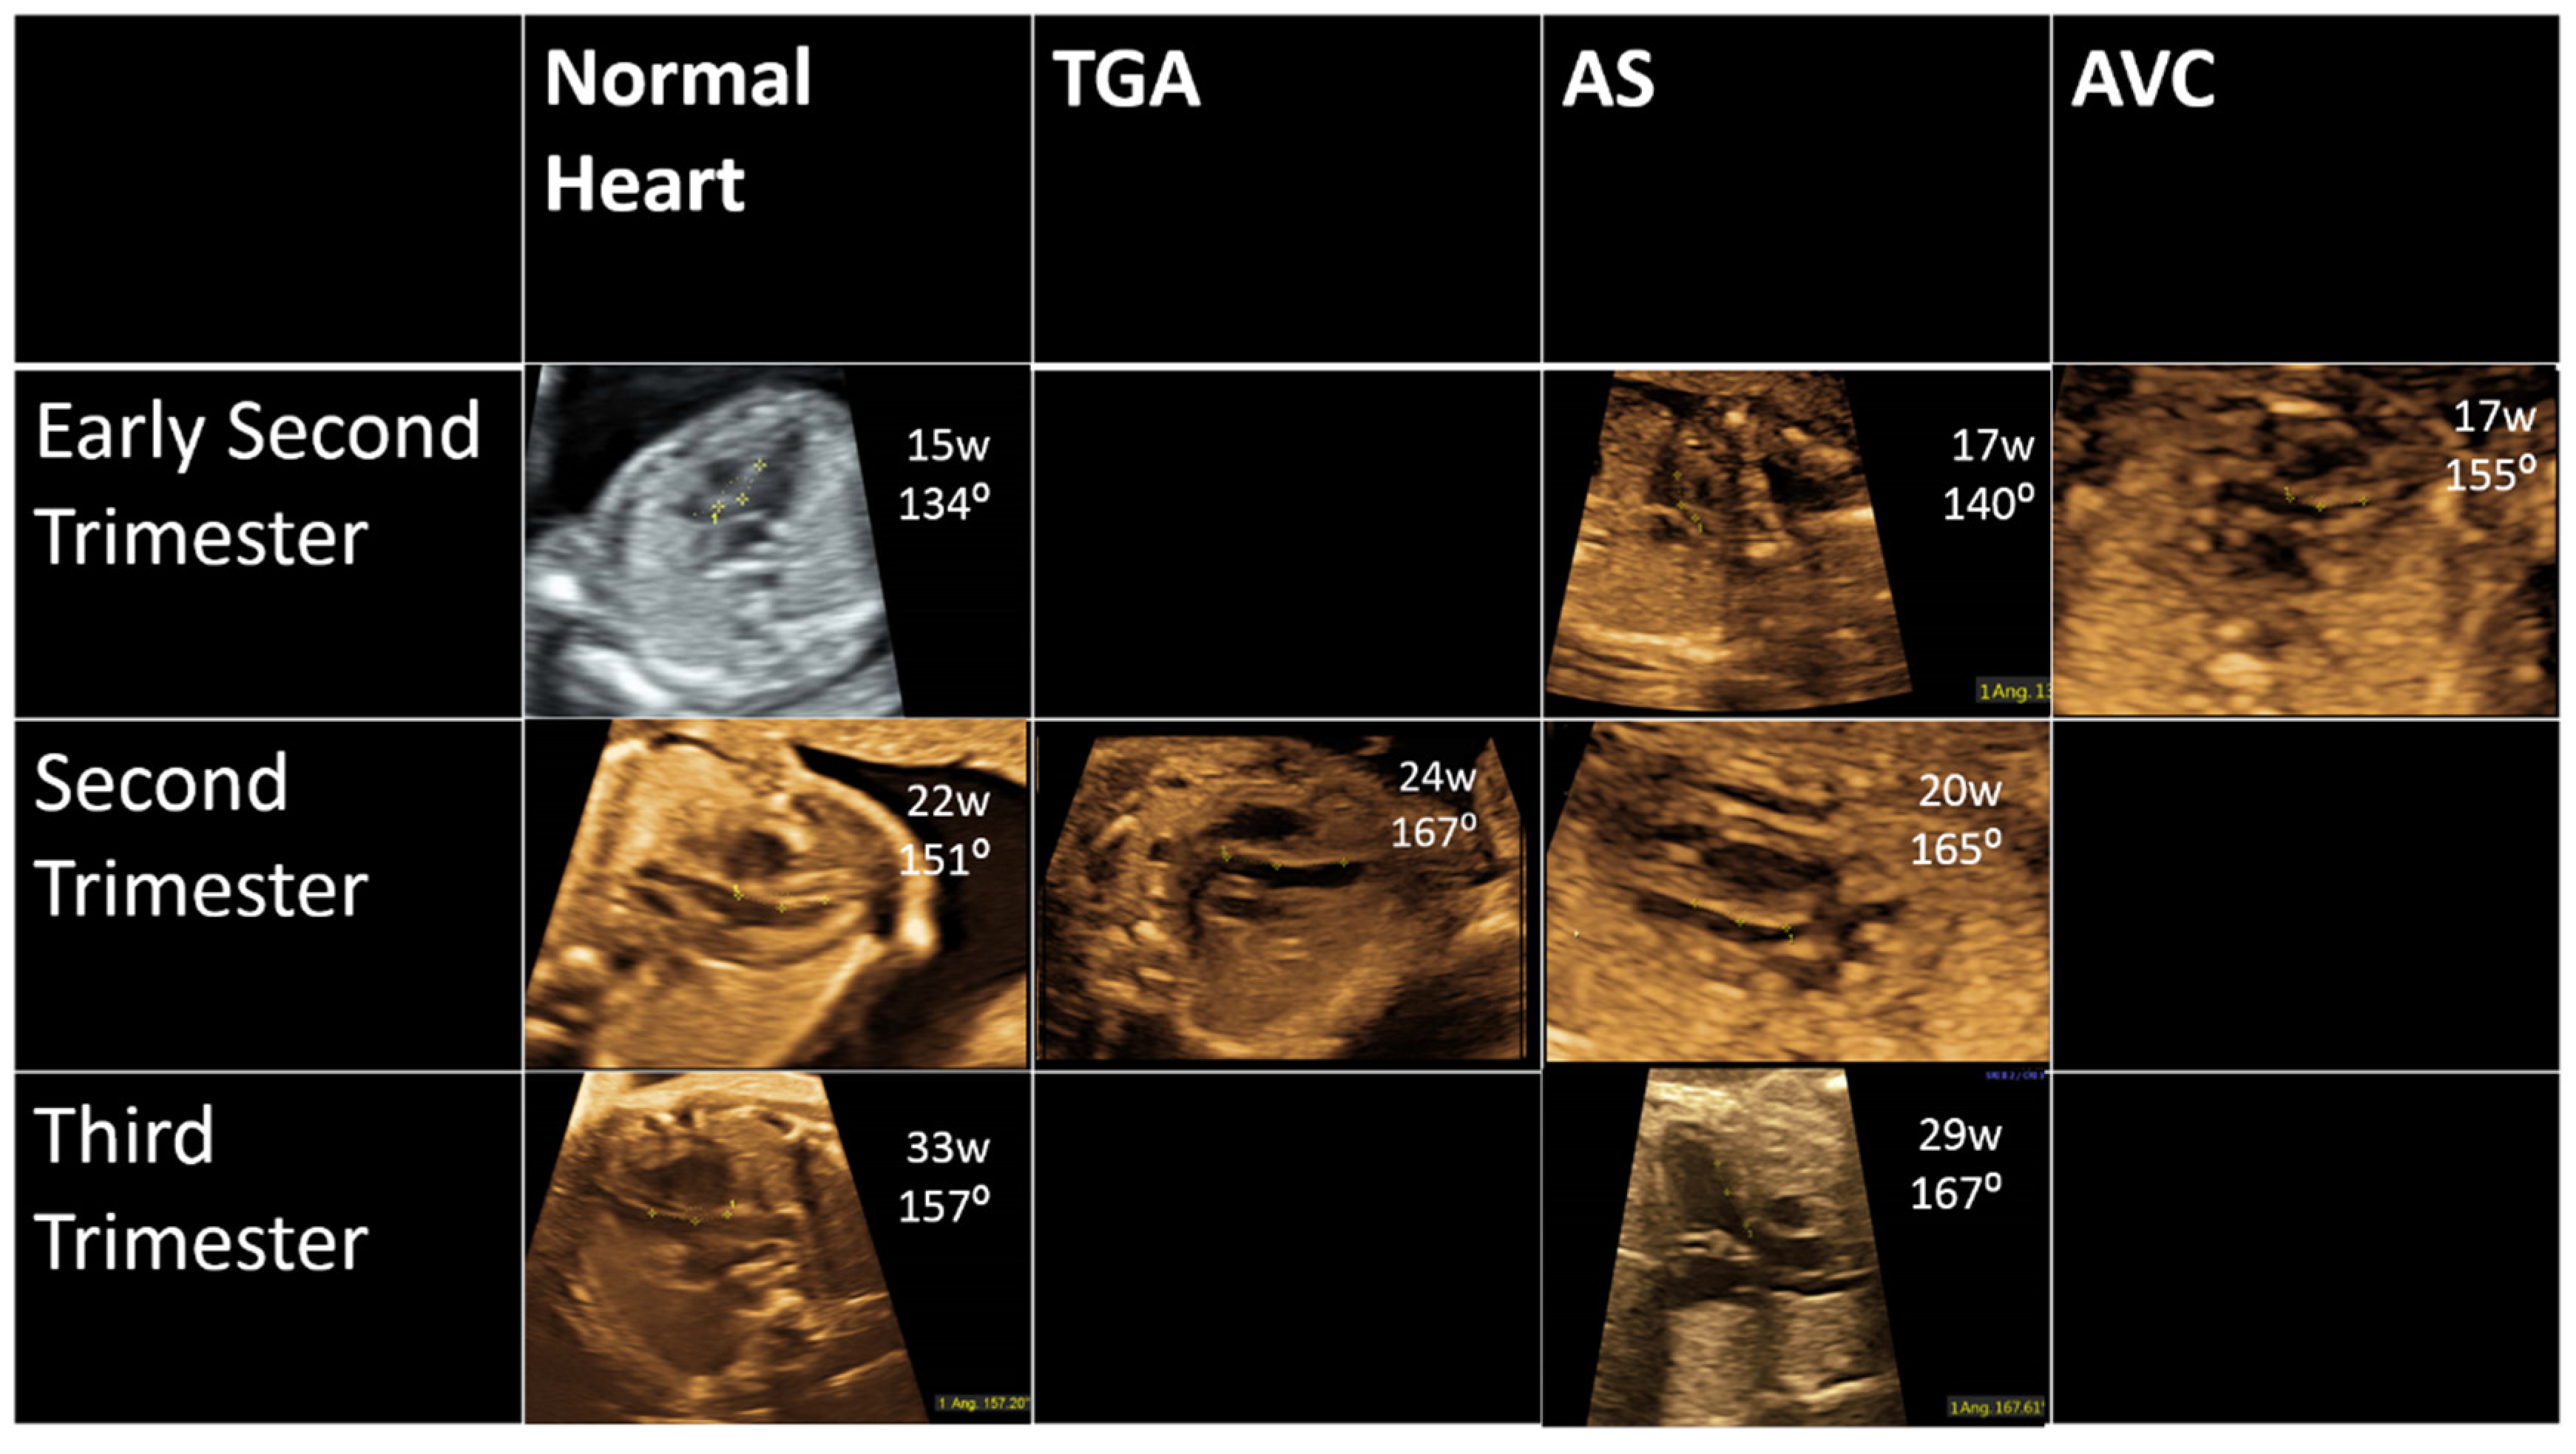

2. Methods

3. Results